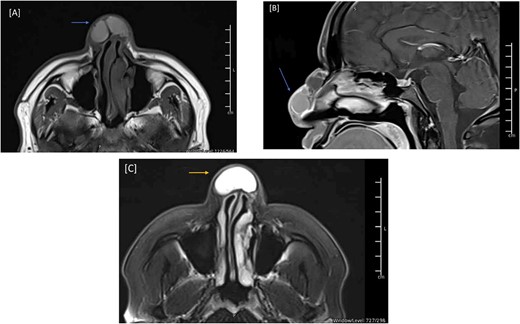

The patient was discharged three days after the surgery with a clean, dry wound and no signs of infection or hematoma collection. The flap was viable with good color and normal capillary refill time. After discharge, the patient had regular follow-ups to assess the wound status and the flap viability. The patient expressed happiness with the shape of his nose. Three months post-op, a follow-up MRI showed total resection of the nasal lesion with no evidence of residuum or recurrence (Fig. 4). The patient was followed in our clinic for 14 months with no signs of recurrence (Fig. 5). During his last visit, he expressed his happiness regarding the relief of symptoms and the shape of his nose.

MRI of the head, and paranasal sinuses (post-op). (A, B) Axial and Mid-sagittal T1 sequence showing total resection of the external nasal mass lesion with a heterogenous enhancement seen likely postoperative changes. No obvious residual mass lesions can be seen.